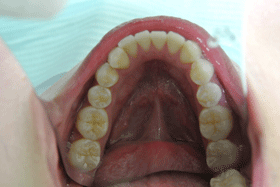

一度も虫歯になってない口腔内

症 例